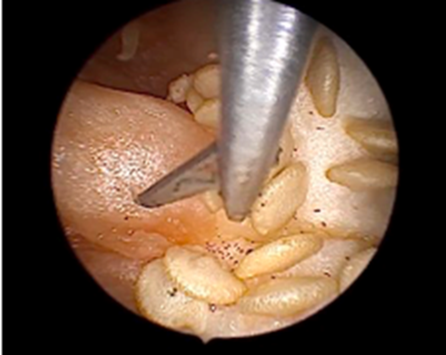

The IAT-BPM was prepared by taking a selection of bell peppers (C. annuum) and cutting a circle around the stem to detach it and clear it out (Figure 7-8). A bit of animal tissue was then secured to the underside of the cut stem using sutures, simulating a pedunculated submucous myoma and secured (Figure 9-10). The stem along with the animal tissue was then placed back on top of the bell pepper and secured with sutures.

A 5mm trocar was used to create an opening, approximately in the midsection on any one of the sides of the pepper as an entry point for the resectoscope. The model was then placed on a suitable stand, placed in a reservoir tray to collect the fluid spill. This was then placed at a convenient height with the monitor placed at a location mimicking the ergonomics of actual surgery. This model was provided at each station. The participants were provided resectoscopes with a bipolar loop electrode, connected to the electrosurgical generator set to the same parameters as actual surgery and given instructions and guidance on its assembly. The trainers emphasized the importance of correct surgical techniques like placing the loop behind the myoma and activating the energy only as the loop moved towards the operating surgeon, never away from him/her. resectoscope with a bipolar loop electrode was then used to practice myomectomy on the animal tissue and shave off bits with the correct technique, while dealing with the problems of vision caused due to bits of tissue and bubbling (Figure 12). At the end of the session, the pepper was cut in half for the trainees to inspect the result of their practice.

Figure 11: Resectoscopic Surgery

Figure 12: Tissue bits and bubbling